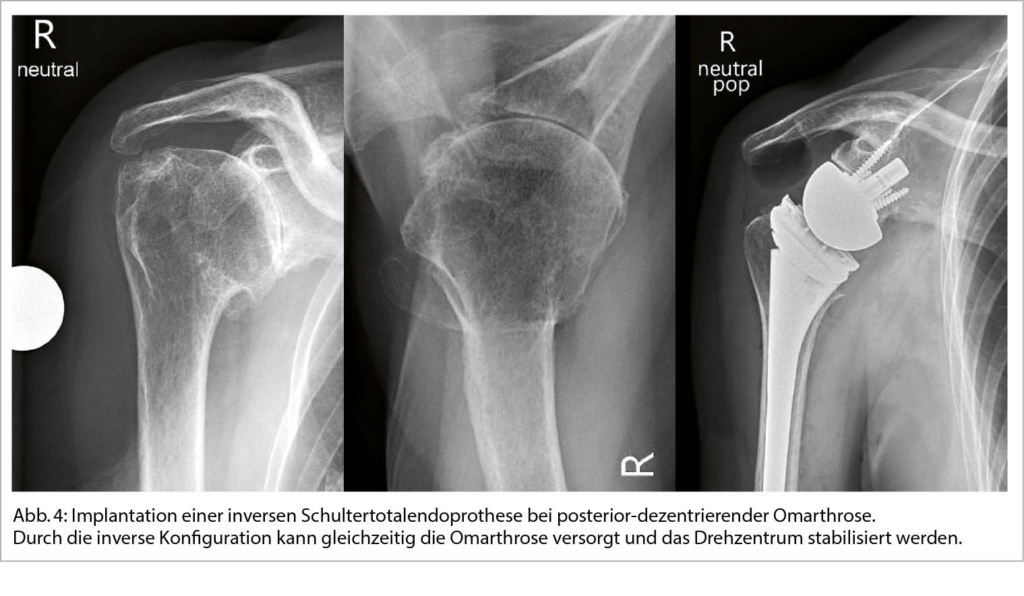

Ist die konservative Therapie ausgeschöpft kann durch die Implantation einer Schulterendoprothese eine zuverlässige Verbesserung der Beschwerden erreicht werden. Die Indikationen zur operativen Versorgung besteht bei therapieresistenten Schmerzen oder unzureichend kompensierbaren Einschränkungen des Bewegungsausmasses sowie zunehmendem Leidensdruck der Patienten. Eine endoprothetische Versorgung kann als anatomische (Total)endoprothese (aTSA) unter Erhalt der ursprünglichen Anatomie oder als inverse Totalendoprothese (rTSA) zur Stabilisierung des Drehzentrums erfolgen (Abb. 4) (12).

Wichtige Strukturen, die zur Zentrierung des Humeruskopfes beitragen sind knöchern die Schultergelenkspfanne sowie weichteilig die Muskeln und Sehnen der Rotatorenmanschette. Exzentrische Omarthrosen aufgrund einer schwerwiegenden Pfannendeformität und statischer Dezentrierung des Oberamkopfes oder aufgrund einer Rotatorenmanschetteninsuffizienz mit instabilem Gelenksdrehzentrum sprechen für die Implantation einer inversen Schulterendoprothese. Der Anteil der implantierten inversen Endoprothesen ist in den letzten Jahren aufgrund der vielfältigen Indikationserweiterungen und nicht zuletzt aufgrund der sehr guten und verlässlich erzielbaren Ergebnisse kontinuierlich gestiegen. Während die inverse Endoprothese durch das stabilere Drehzentrum überzeugt, ist bei der anatomischen Endoprothese das durchschnittlich zu erwartende postoperative Bewegungsausmass grösser. Bei Verlust der Stabilität des Drehzentrums im Verlauf nach Implantation einer anatomischen Schultertotalendoprothese aufgrund einer sekundären Rotatorenmanschetteninsuffizienz oder eines zunehmenden exzentrischen Pfannenabriebes ist der Wechsel auf eine inverse Prothese möglich (13).